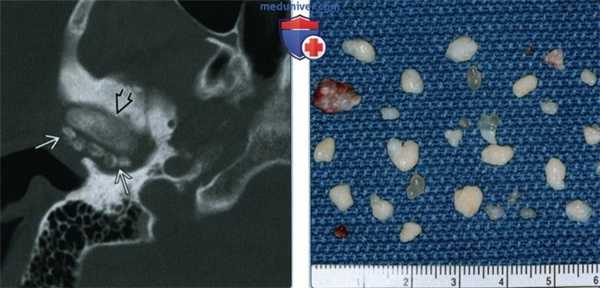

(Слева) При аксиальной КТ в костном окне в правом височно-нижнечелюстном суставе (ВНЧС) визуализируются множественные мелкие кальцинированные узелки. Мыщелок склерозирован, слегка деформирован, суставное пространство сужено в передних отделах из-за дегенеративных изменений.

(Справа) Макропрепарат, определяются кальцинированные свободные тела, извлеченные из височно-нижнечелюстного сустава, пораженного синовиальным хондроматозом. Обратите внимание на различные размеры этих тел (2-10 мм).

3. КТ при синовиальном хондроматозе височно-нижнечелюстного сустава:

• КТ в костном окне:

о Множественные обызвествленные узелки вокруг мыщелка нижней челюсти

о Часто также обнаруживаются дегенеративные изменения суставной поверхности мыщелка